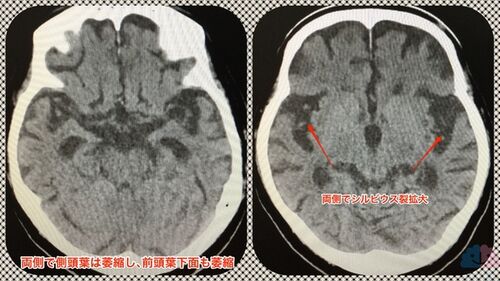

【症例報告】前頭側頭型認知症の方。2年4ヶ月のお付き合いの末、かかりつけ医変更に。

今回紹介するのは、前頭側頭型認知症のHYさん。 初診時は60代後半。それまでアルツハイマー型認知症の診断でドネペジルが処方されていた。 約2年4ヶ月の経過を、ほぼカルテからの引用で紹介する。ご家族や施設スタッフ、ケアマネさん達と情報をやりとりしながら、皆…